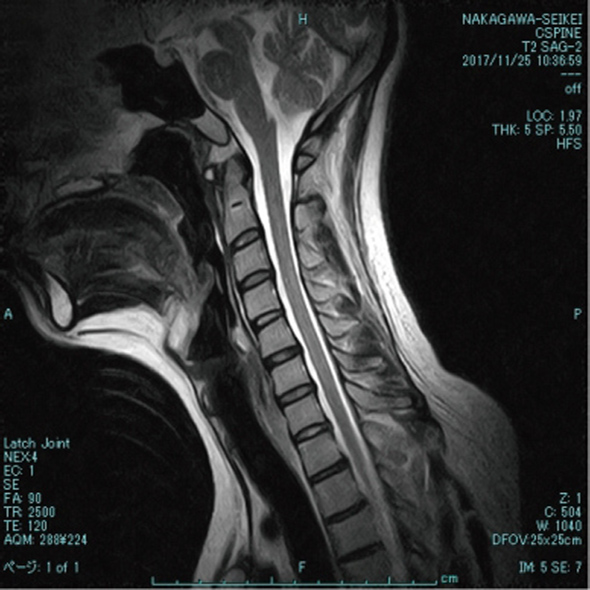

当院では新世代のオープン型MRIを導入しております。従来のMRIより圧迫感がなく、撮影時の「音」も静かになっています。事故の症状、痛みの部位などを画像診断にてしっかりと検査していきます。

交通事故治療は画像診断が不可欠です。

MRIは骨挫傷・神経圧迫・椎間板の突出、靭帯損傷などを診断することができます。